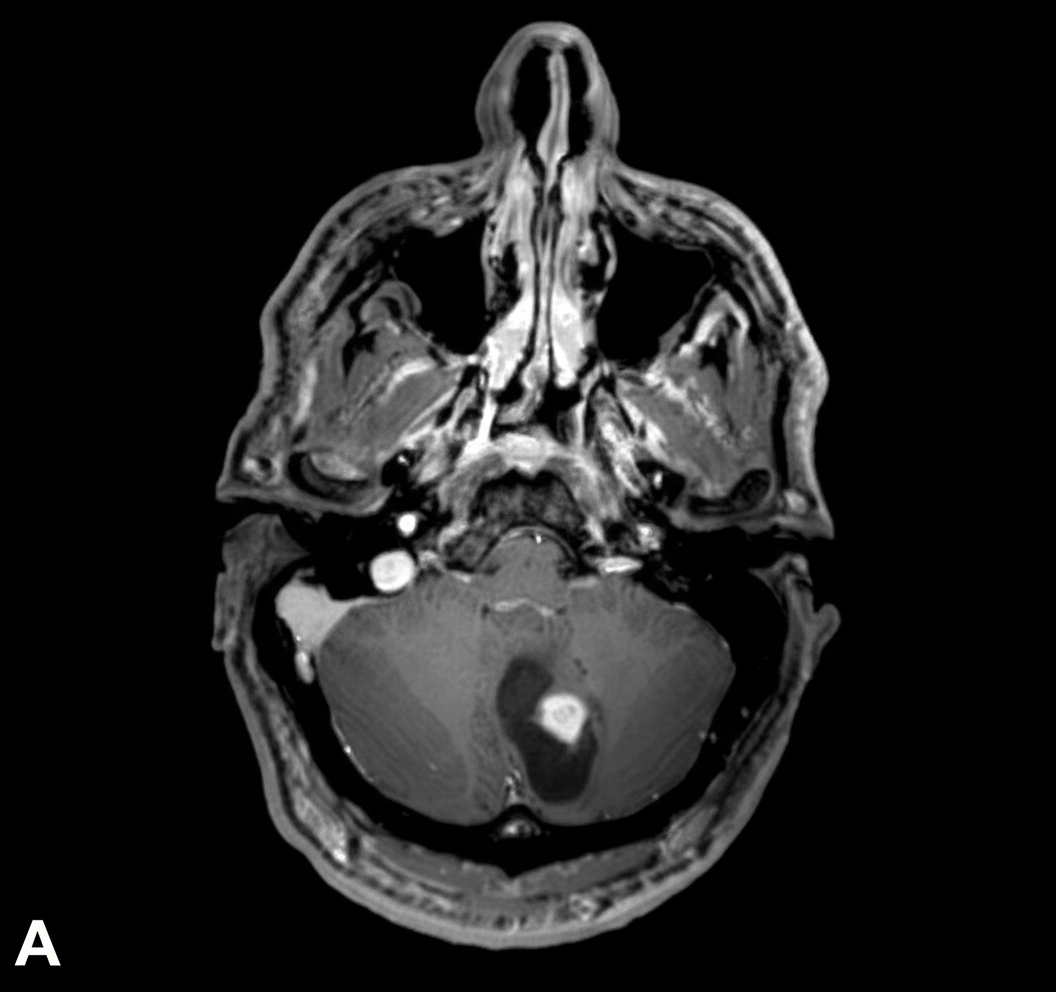

A 9-year-old girl is brought to her primary care physician because of a 4-month history of early morning headaches and worsening fatigue. The headaches are often accompanied by nausea and sometimes relieved by vomiting. She stopped going to her ballet lessons 2 weeks ago because she was embarrassed about falling frequently and having increasing difficulty performing the steps. Her temperature is 36.8°C (98.2°F), pulse is 98/min, and blood pressure is 105/65 mm Hg. She has a broad-based gait. While standing with both feet together and raising her arms, closing her eyes does not affect her balance. She is unable to perform rapid, alternating movements with her hands. An MRI of the brain is shown. Which of the following is the most likely diagnosis?